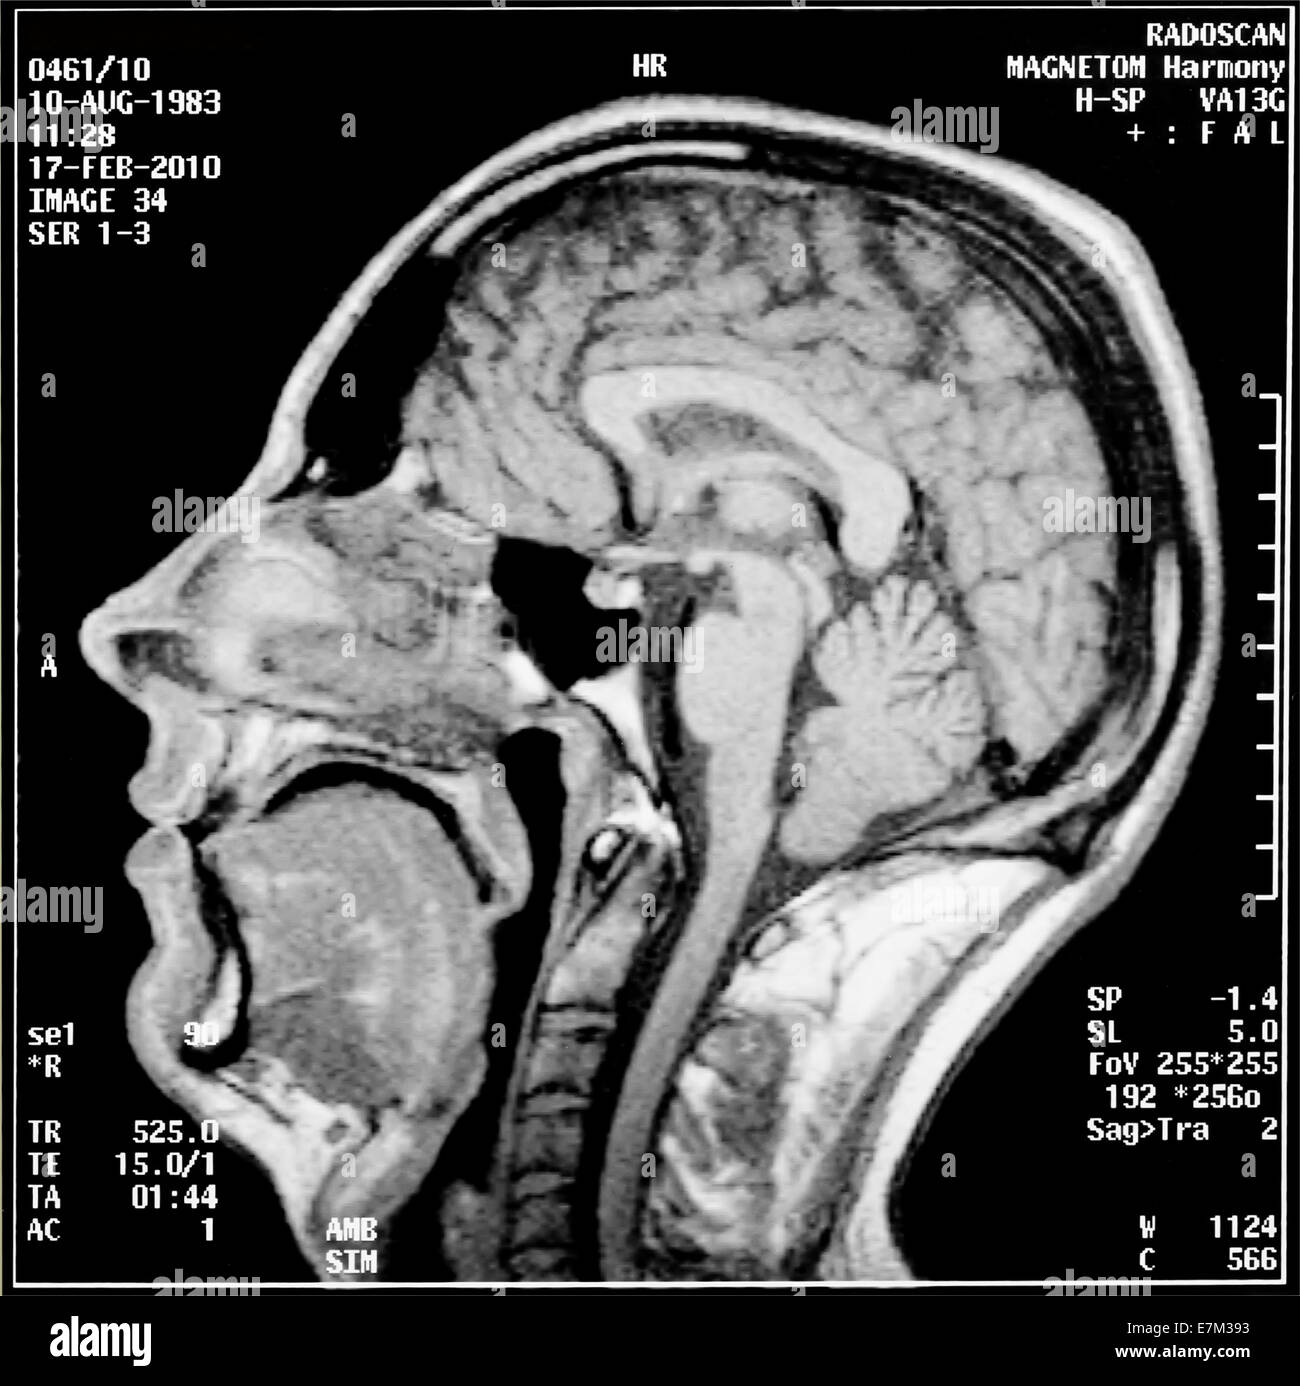

Lista muestra hermosas imágenes de resonancia magnética cerebral normal y anormal dinosenglish.edu.vn para que puedas explorar más en detalle.

resonancia magnética cerebral normal y anormal Pin en NEUROCIENCIAS resonancia magnética de cerebro Resonancia magnética (RM) de cerebro, corte axial ponderado en T2: la … VIDEO Nueva mancha en la Resonancia

Engineer Team : RESONANCIA MAGNETICA Magnetic Resonance Imaging – Clinical Images Hallazgos por resonancia magnética cerebral de nuestro paciente. M, 21 … Imágenes por resonancia magnética anormales como predictoras de mal … Imágenes por resonancia magnética anormales como predictoras de mal … Lesiones en resonancia magnética (RM) del encéfalo y la médula espinal … Pin en Resonancia Magnética del Encéfalo A) Resonancia magnética cerebral (RMC) mostrando infartos en … Caso 1: Edema cerebral visualizado mediante RM. (A) Secuencia T1 plano … Rascacielos dormir pasta tac y resonancia diferencias retrasar … Pin on Apuntes de Enfermería y T.C.A.E Resonancia magnética cerebral secuencia T2, que muestra lesión … Meningitis aguda en la enfermedad de Behçet | Reumatología Clínica Resonancia magnética coronal normal del cerebro Fotografía de stock – Alamy Imágenes de resonancia magnética, la imagen de la cabeza en diferentes … Resonancia magnética cerebral A) protocolo T1 sagital (Caso 1). Se … Resonancia magnética cerebral. Secuencia T1 corte sagital. Atrofia … Resonancia magnética de cerebro, cortes axiales, secuencias T2. Señal … Resonancia magnética de cráneo. A y B) Cortes axiales FLAIR … Resonancia magnética (RM) de cerebro, corte axial ponderado en T2: la … RM cerebral: Interpretación paso a paso | Kenhub Resonancia magnética de cerebro, cortes axiales, secuencias T2. Señal … De Resonancia Magnética De Cerebro Foto de archivo – Imagen de arteria … Top 107+ Imagenes de resonancia cerebral normal – Destinomexico.mx -Imagen por resonancia magnética del cerebro. a) Cortes sagital y axial … resonanCia magnétiCa Cerebral donde se observa hiperintensidad a nivel … MRI (Imagen de resonancia magnética) – Tomografía computarizada de la … Meningioma – NCI Imágenes por resonancia magnética coloreadas del cerebro sano del … Resonancia magnética cerebral en secuencia FLAIR, que muestra lesiones … Contraste resonancia magnetica cerebral – senturinthegreen Relación de los espacios de Virchow-Robin con la enfermedad de … Gliomatosis cerebral – Instituto Nacional del Cáncer Pin en Neurology. Recomendaciones para la utilización e interpretación de los estudios de … Fotografía De La Proyección De Imagen De Resonancia Magnética Del … atmósfera Dirigir Cumplir anatomia resonancia magnetica Desarrollar … Pin en #MEDICINA,#SALUD Resonancia magnética de la nasofaringe De Resonancia Magnética De Cerebro Foto de archivo – Imagen de polilla … Atrofia cortical global de predominio parietal en la Resonancia … Resonancia magnética cerebral | Download Scientific Diagram Neuroblog: Resonancia magnética cerebral en la trombosis crónica de … De Resonancia Magnética De Cerebro Imagen de archivo – Imagen de … ¿Cuáles son los riesgos de la resonancia magnética? – Integra Salud … Resonancia magnética cerebral al decimocuarto día de ingreso: área … Resonancia magnética. Corte axial mostrando área infartada en el … Resonancia magnética cerebral del paciente AV evidenciando lesiones en … -Ressonância magnética de encéfalo mostrando múltiplas imagens … Resonancia magnética cerebral secuencia FLAIR (Fluid Attenuated … Resonancia magnética cerebral con protocolo de epilepsia, en sección … Resonancia magnética cerebral en corte sagital. Se observa una evidente … Resonancia magnética craneal en la que se evidencian lesiones … Logran visualizar el cerebro a detalle más completo tras una resonancia … Así decide el cerebro la severidad de un castigo De Resonancia Magnética De Cerebro, Imagen de archivo – Imagen de … A) Resonancia magnética cerebral; Secuencia Tof: oclusión de arteria … Un estudio asocia la ansiedad con la aparición rápida del Alzheimer IMÁGENES DE 18 F-PR04.MZ PET FUSIONADA CON RESONANCIA MAGNÉTICA … Imágenes por resonancia magnética anormales como predictoras de mal … Tumores de la región pineal – Instituto Nacional del Cáncer Epilepsia: una historia de voces y fantasmas | Neurología Contribución de las imágenes de resonancia magnética por tensor de … Resonancia magnética secuencia T2 plano coronal de quiste epidermoide … Resonancia Magnética Cerebral del paciente: a. Aumento de… | Download … Resonancia magnética cerebral 2022 Síndrome de hemiconvulsión-hemiplejía-epilepsia. Seguimiento de un caso … Enfoque Radiologico: La resonancia magnética permite detectar lesiones … Resonancia magnética craneal T1 con contraste que muestra angiomatosis … guidewiz – Blog Resonancia magnética cerebral, secuencia SWI. Ribete hipointenso en la … resonAnCiA mAgnétiCA de ColumnA Con gAdolinio. Corte sAgitAl en t1 de … SEMANA 12: FUNDAMENTOS DE RESONANCIA MAGNÉTICA NUCLEAR. INDICACIONES Y … DIAGNÓSTICO DE ESCLEROSIS MÚLTIP Magnetic resonance imaging of the brain – Alchetron, the free social … Resonancia magnética de órbitas | Instituto Radiológico Dr. E Castillo Alteración de la marcha en un paciente post-trasplante hepático Resonancia magnética cerebral de un paciente sano (Ay B) y paciente que … Utilidad de la resonancia magnética craneal para el diagnóstico de la … Resonancia Magnética Del Cerebro El Tumor Cerebral Foto de stock y más … De Resonancia Magnética De Cerebro Imagen de archivo – Imagen de … ABDALLA RADIOLOGIA: NEURINOMA ACUSTICO Atrofia cortical global de predominio parietal en la Resonancia … Resonancia Magnética : Producción de la imagen MRI Brain Scan — Stock Photo © Bunyos30 #18724051 Mri (imagen de resonancia magnética) Monitor con imagen de captura de … Tomografía computarizada vs resonancia magnética: diferencia y … Tumores Cerebrales – Unidad de Neurocirugía RGS Resonancia magnética de la columna, sección sagital. Observe los discos … La resonancia magnética, una técnica imprescindible en el diagnóstico … Perfusión Cerebral por Resonancia Magnética | ¿Qué es? ¿Necesita Contraste? Resonancia Magnética Cerebro A: resonancia magnética, T2 coronal preoperatoria; se observa lesión en … Resonancia magnética cerebral — Foto de stock © Bunyos30 #27340623 La resonancia magnética se perfila como detector de mentiras | Futuro … Resonancia magnética cerebral en T1 con gadolinio, cortes axial (a … MRI brain : show brain tumor at right parietal lobe of cerebrum — Stock … NEUROIMÁGENES EN ENFERMEDAD DE PARKINSON: ROL DE LA RESONANCIA …